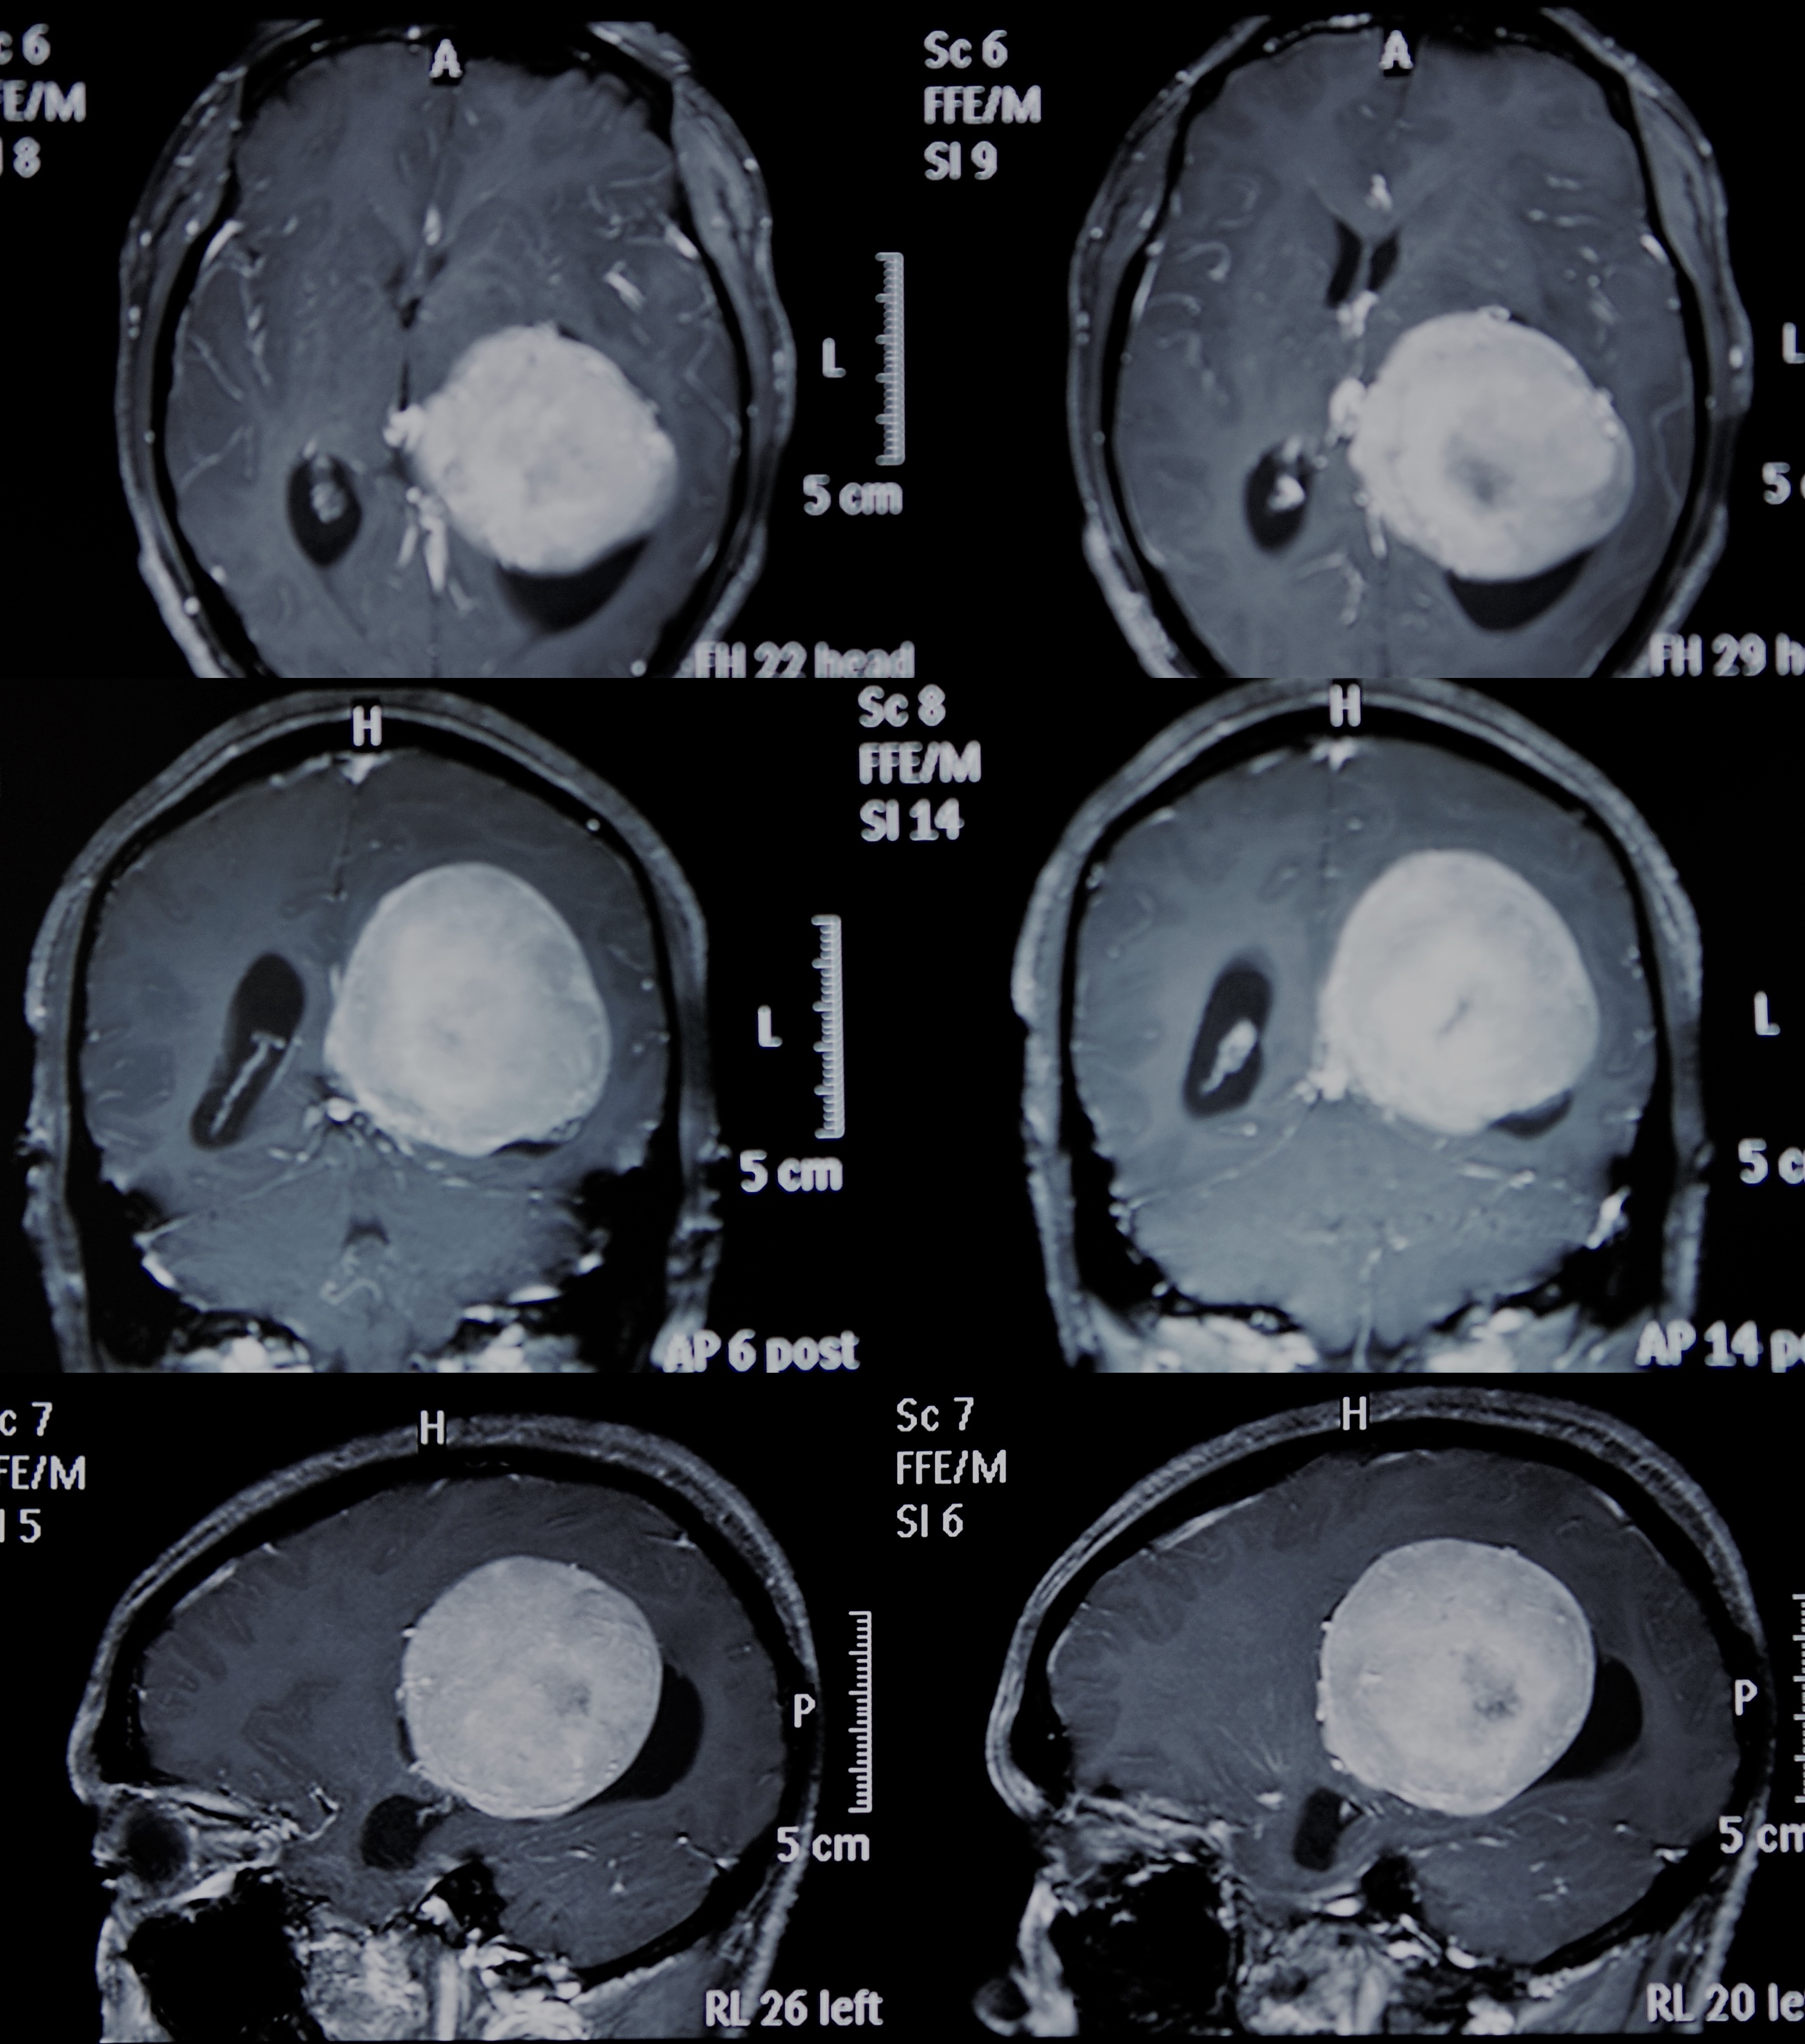

右侧顶叶窦镰旁脑膜瘤一例 - 神经外科专业讨论版 - 爱爱医医学论坛

图片尺寸3264x2448